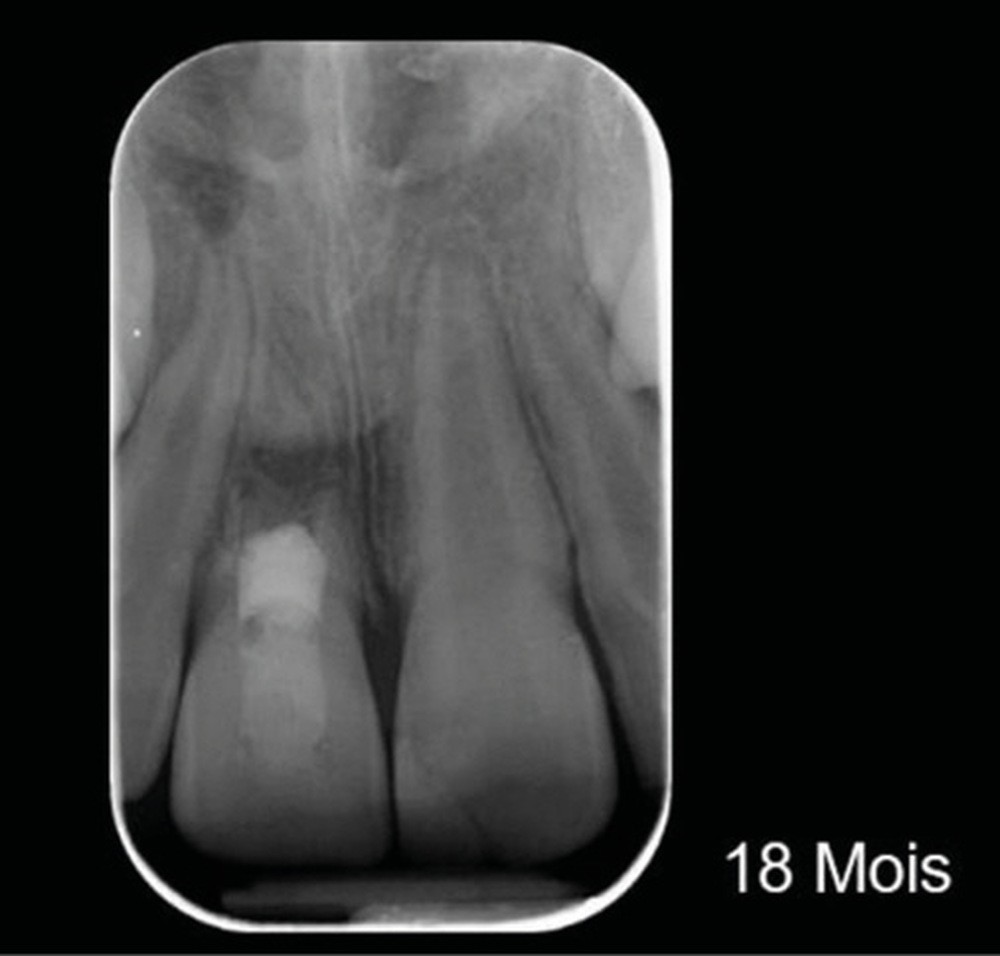

Ce cas clinique est particulier et illustre parfaitement l’évolution que suit l’endodontie depuis une dizaine d’années. Sans entrer dans le détail technique, cette dent expulsée avait été repositionnée dans son alvéole et un premier traitement de régénération intracanalaire tenté. Malheureusement suivi d’un échec. Le jeune âge de la patiente a été une motivation particulière pour tout tenter dans le but, au moins, de gagner du temps. Après plusieurs séances d’hydroxyde de calcium, l’apexification a été réalisée comme cela était possible. Le contrôle à 18 mois confirme que l’acharnement a payé.

Plus que sur l’éventuelle « prouesse technique » – qu’en tant que praticien nous pouvons être tentés de saluer –, il faut s’arrêter sur la facilité qu’a la biologie de stabiliser une situation pourtant désespérée, lorsque les conditions de remise en conditions saines sont mises en place.